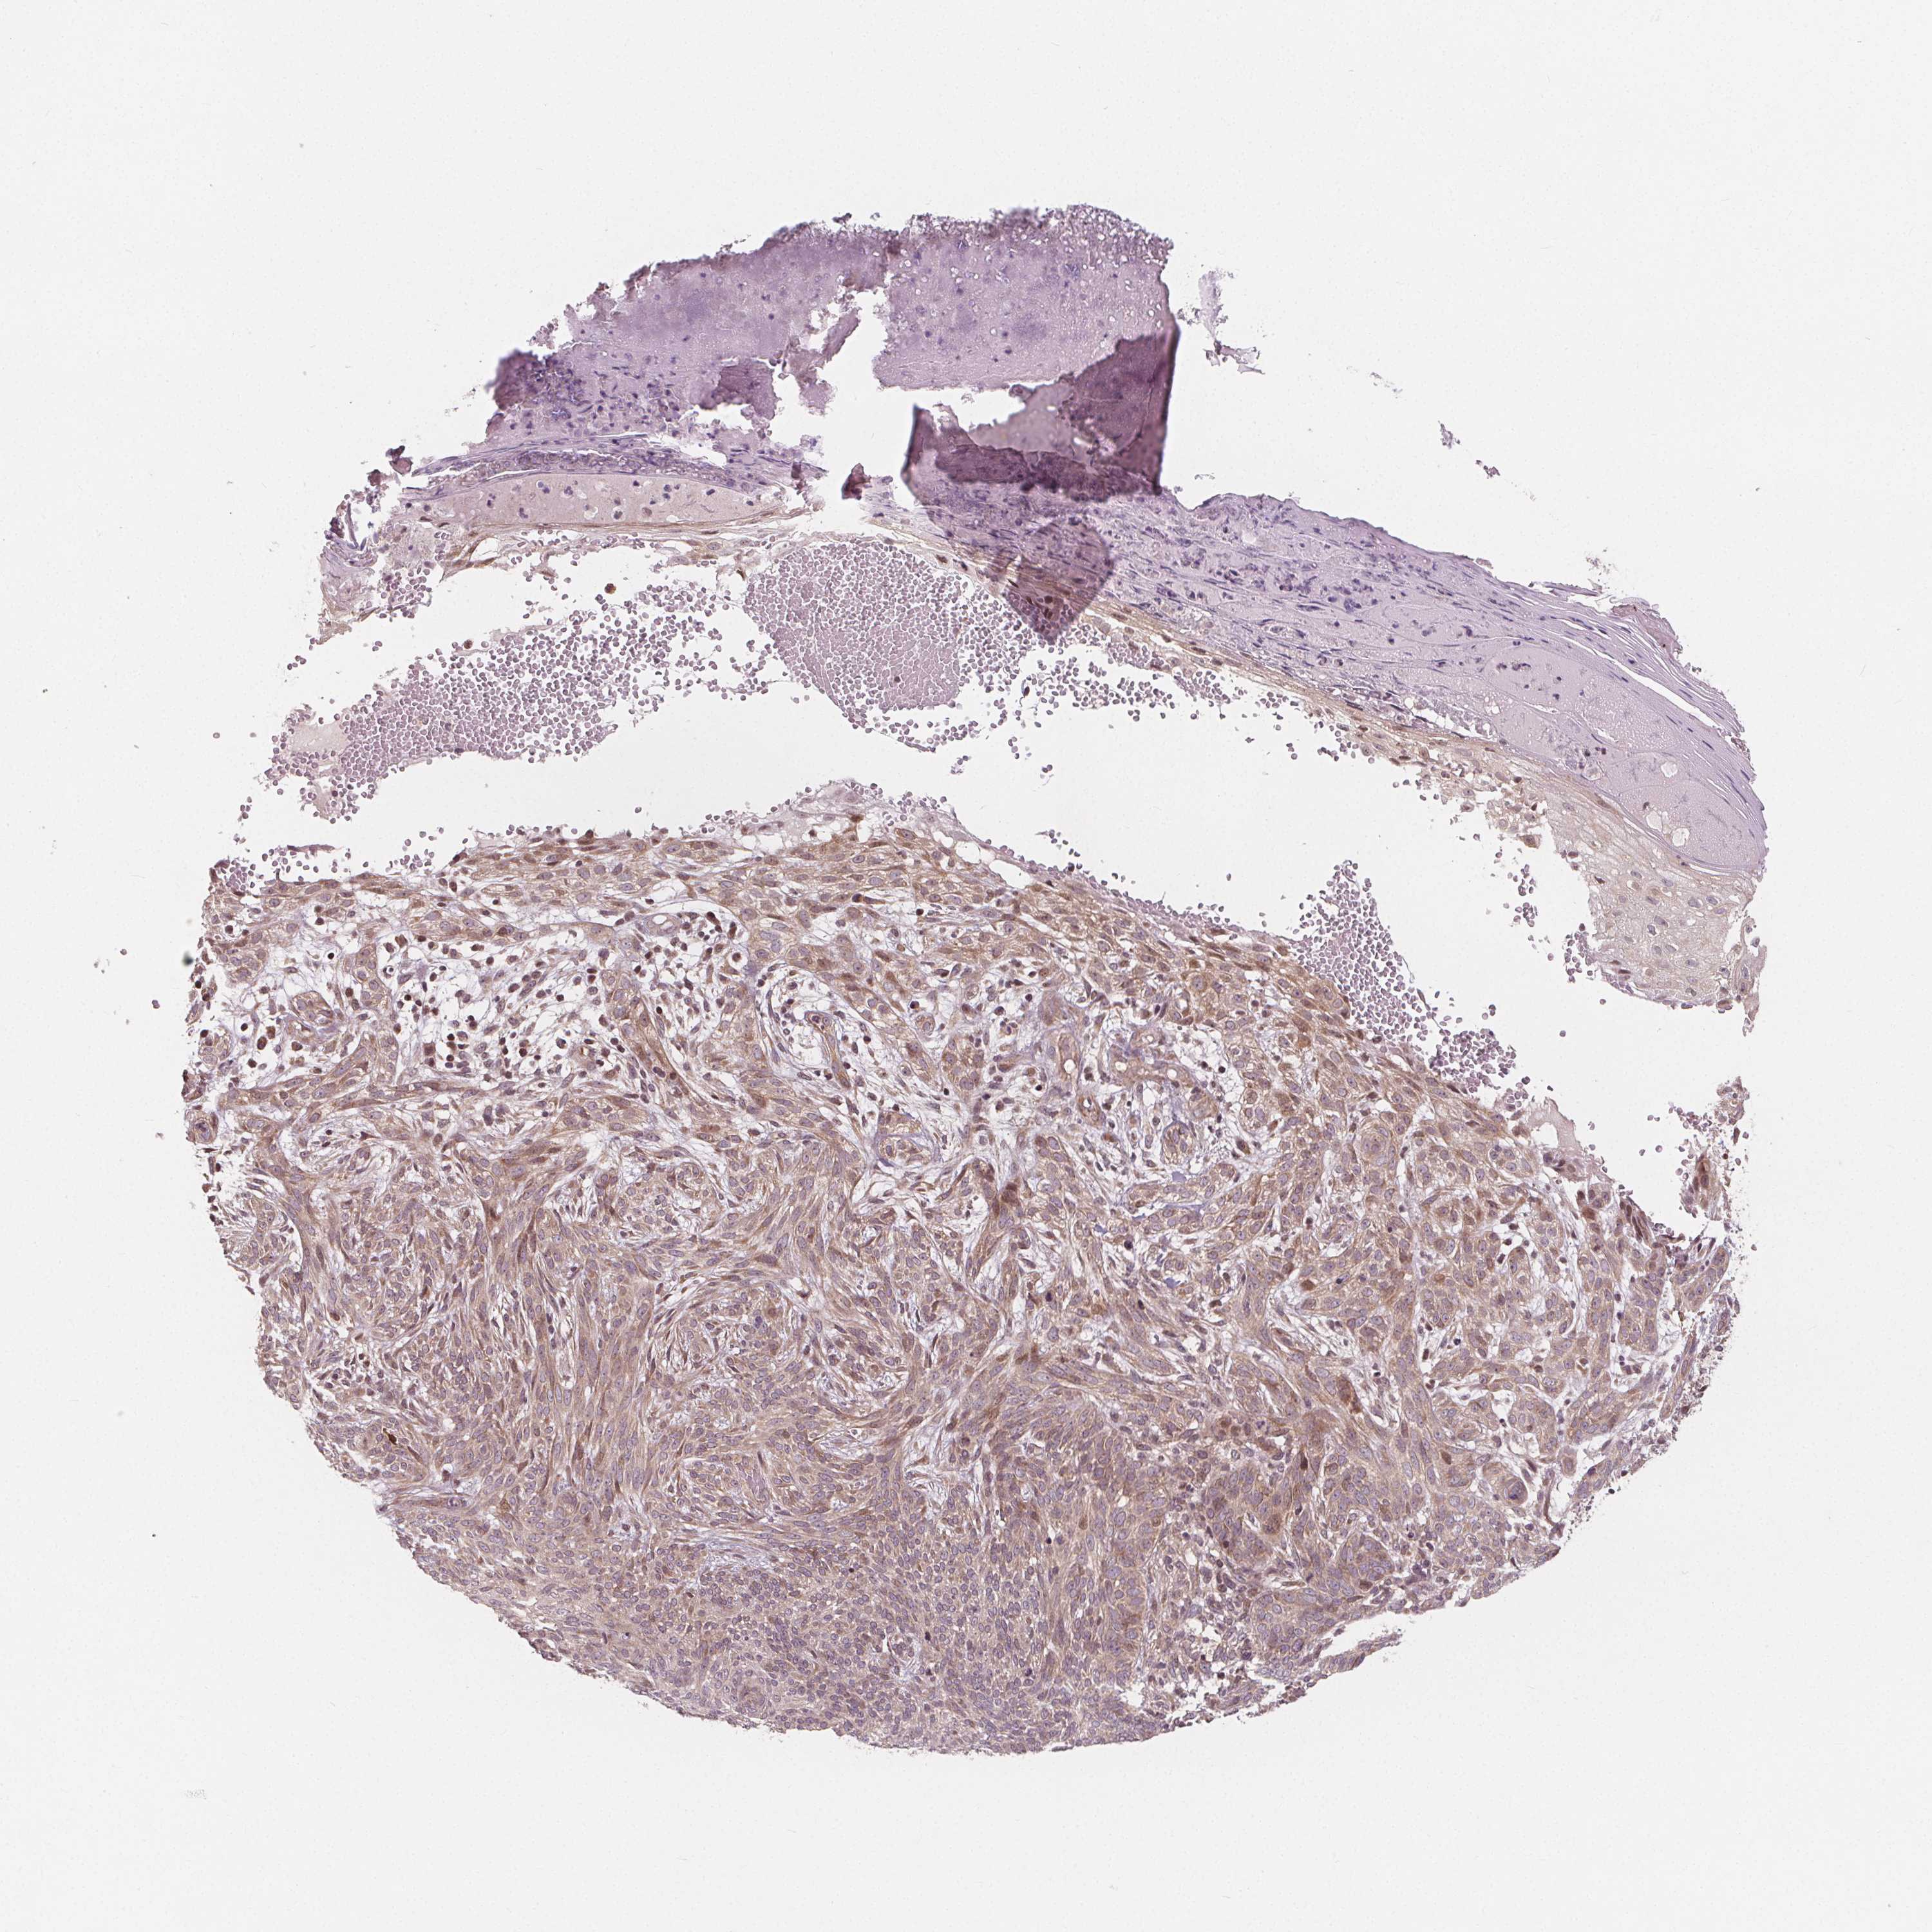

SKIN CANCER - Protein expressioni

A mouse-over function shows sample information and annotation data. Click on an image to view it in a full screen mode. Samples can be filtered based on level of antibody staining by selecting one or several of the following categories: high, medium, low and not detected. The assay and annotation is described here.

Each image is clickable and will lead to virtual microscopy that enables deeper exploration of all samples and also displays staining intensity scores, fraction scores and subcellular localization as well as patient and tissue information for each sample.

Antibody HPA064427

Antibody CAB021903

Staining

High

Medium

Low

Not detected

Intensity

Strong

Moderate

Weak

Negative

Quantity

>75%

75%-25%

<25%

None

Location

Nuclear

Cytoplasmic/membranous

Cytoplasmic/membranous,nuclear

Basal cell carcinoma

BCC, high aggressive

Squamous cell carcinoma, NOS